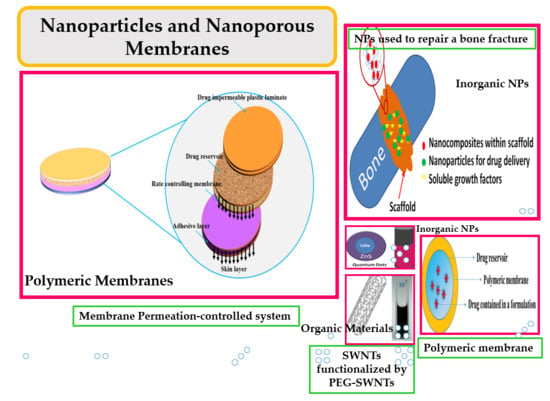

:1. Introduction

1.1. Why Nanoparticles?

1.2. Why a Nanoporous Membrane?

2. Drug Delivery System

3. Inorganic NPs for Hard Tissue Regeneration

5. Porous Membranes

5.2.1. Polymeric Membranes